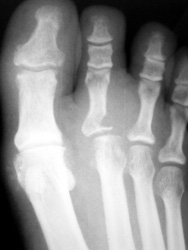

Deposition of urate and CPPD crystals in periarticular tissues. Usually present as soft tissue swelling and sharply defined punched out erosions with overhanging margins.

44years old male with rapidly enlarging mass in the foot. Radiographs demonstrates soft tissue mass between the 2nd and 3rd toes,with no calcification.Well defined erosion is noted at the radial aspect of the base of proximal phalanx of 2nd toe. Mild soft tissue swelling with faint calcification is also seen at 1st MTP joint ,with small erosion medial aspect of 1st Mt head. MR demonstrates mass is isointense to hypointense on T1W, and T2W images, with minimum bone marrow edema at the base of proximal phalanx of 2nd toe. Erosion is well seen at the base of proximal phalanx of 2nd toe on T1W images.